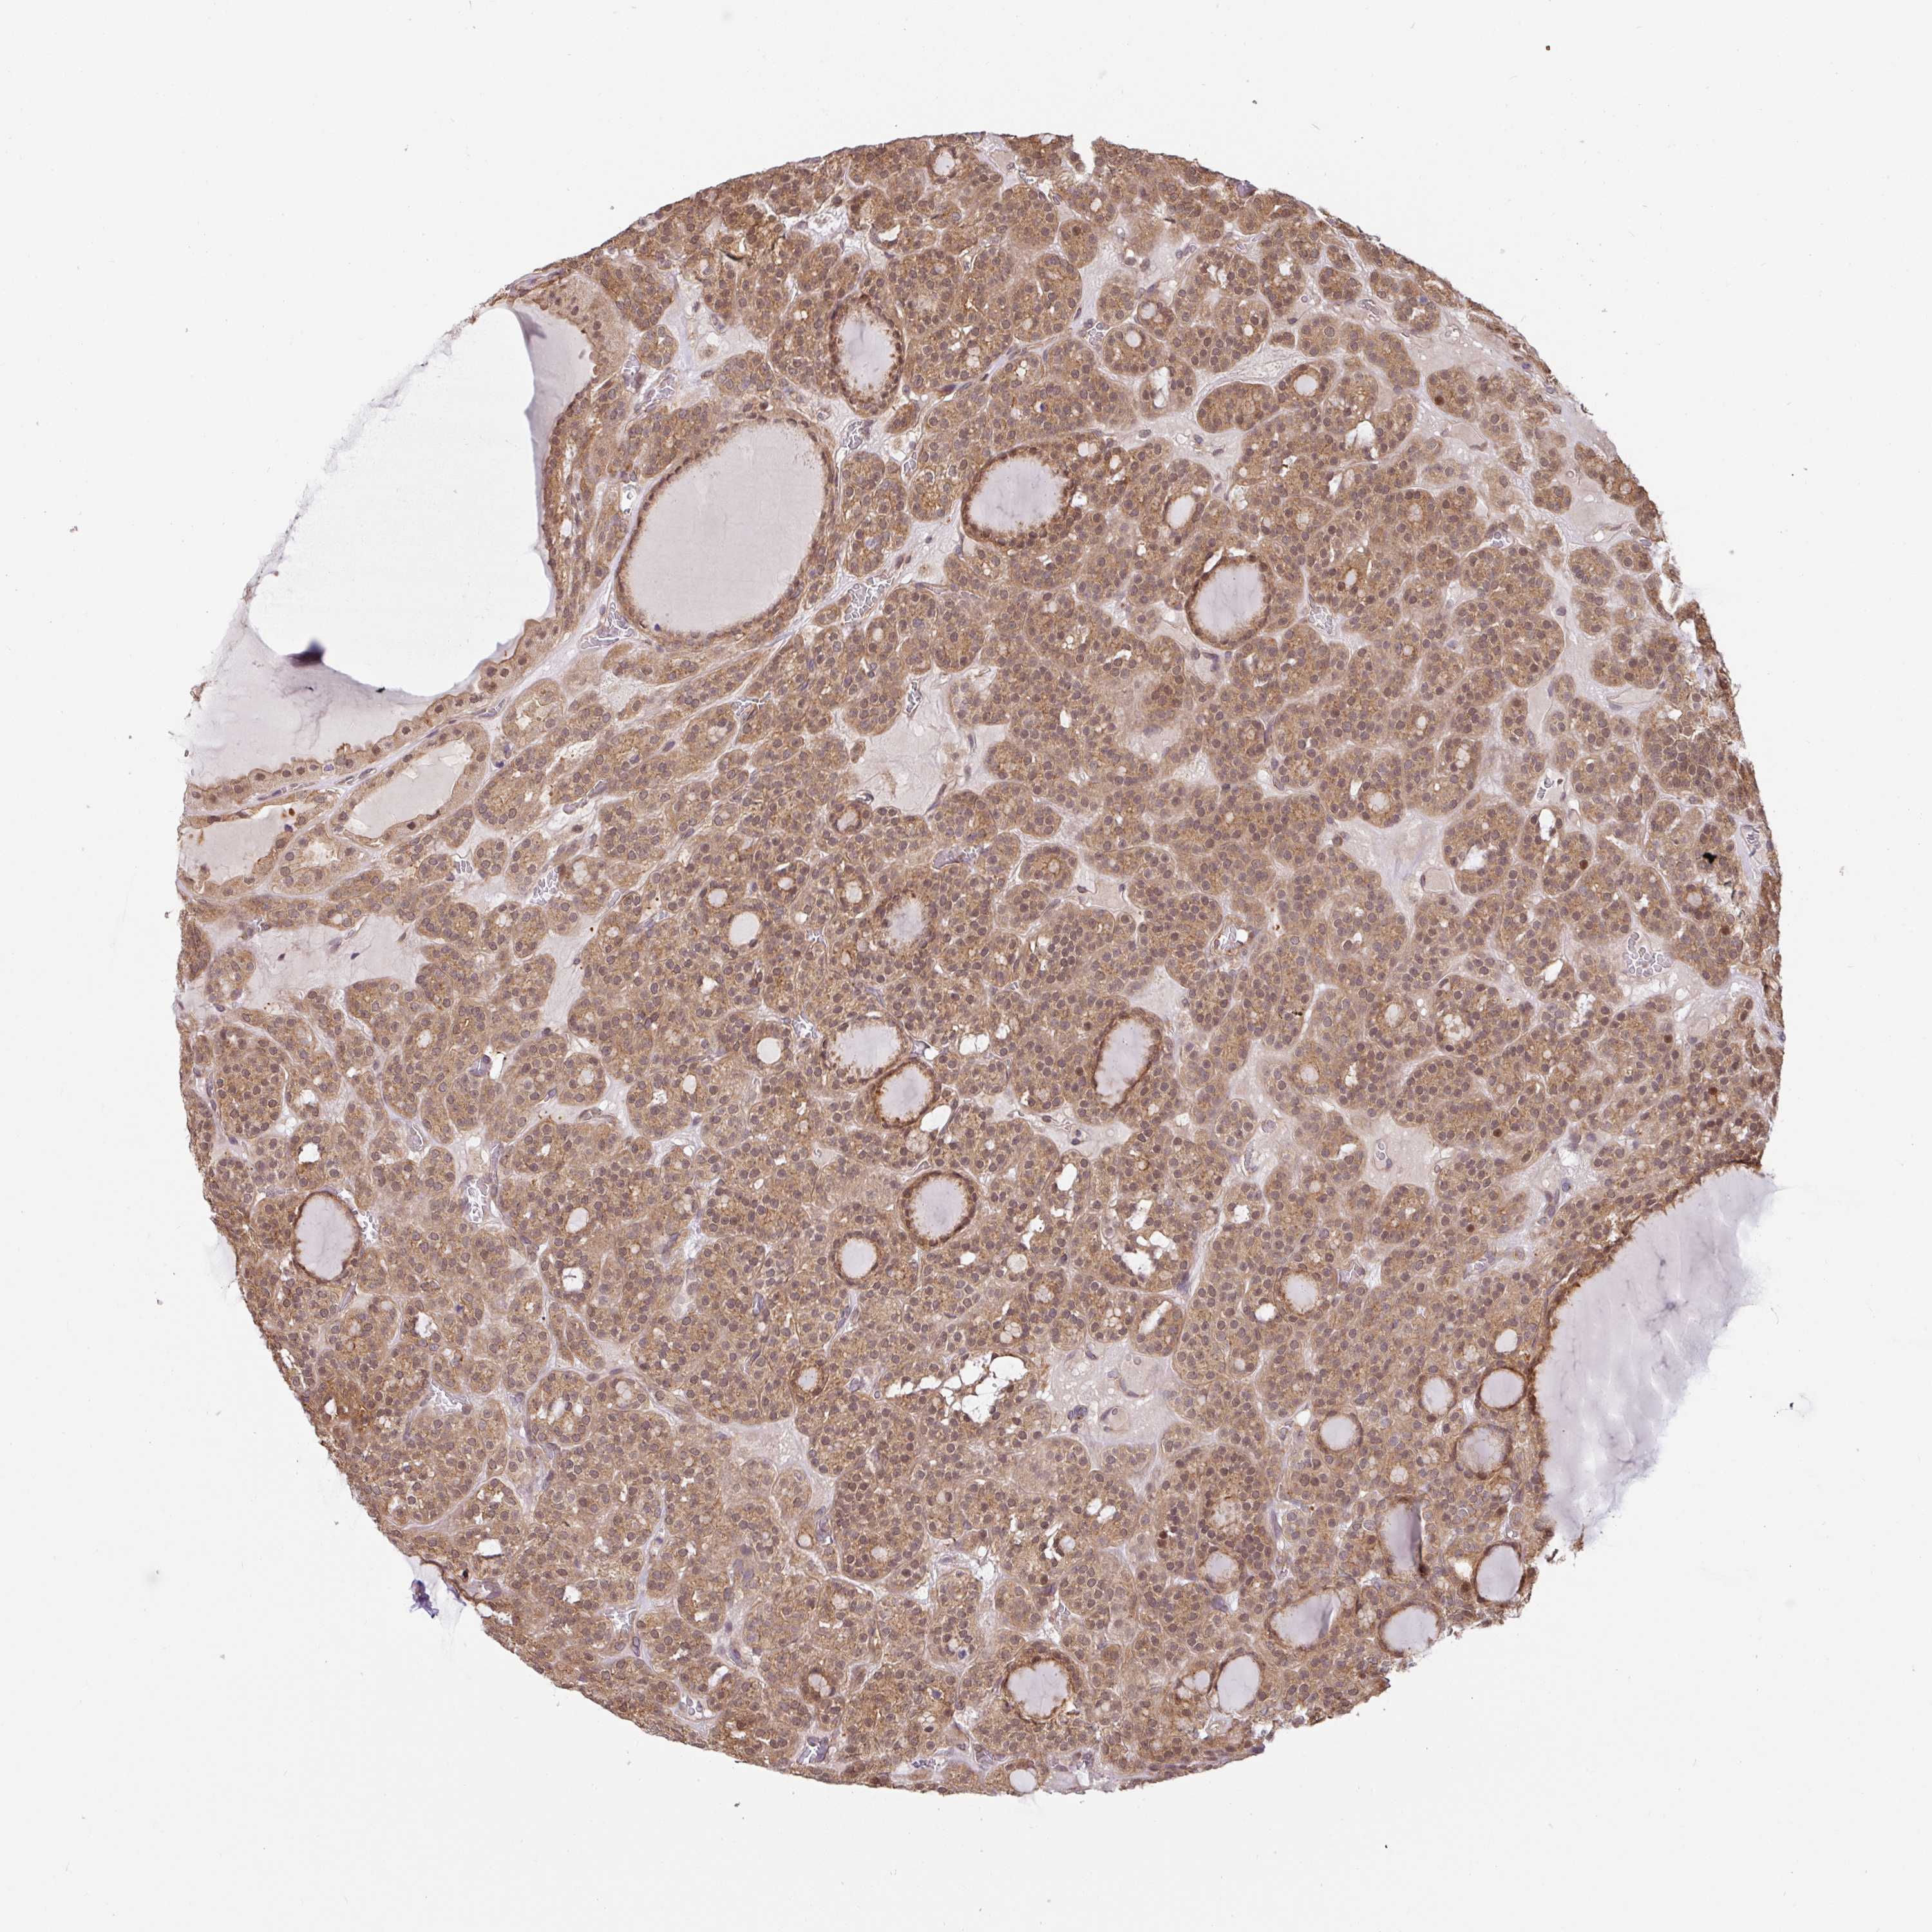

THYROID CANCER - Protein expressioni

A mouse-over function shows sample information and annotation data. Click on an image to view it in a full screen mode. Samples can be filtered based on level of antibody staining by selecting one or several of the following categories: high, medium, low and not detected. The assay and annotation is described here.

Note that samples used for immunohistochemistry by the Human Protein Atlas do not correspond to samples in the TCGA dataset.

Antibody stainingi

Antibody staining in the annotated cell types in the current human tissue is reported as not detected, low, medium, or high, based on conventional immunohistochemistry profiling in selected tissues. This score is based on the combination of the staining intensity and fraction of stained cells.

Each image is clickable and will lead to virtual microscopy that enables deeper exploration of all samples and also displays staining intensity scores, fraction scores and subcellular localization as well as patient and tissue information for each sample.

Antibody HPA049911

Antibody CAB010161

Staining

High

Medium

Low

Not detected

Intensity

Strong

Moderate

Weak

Negative

Quantity

>75%

75%-25%

<25%

None

Location

Nuclear

Cytoplasmic/membranous

Cytoplasmic/membranous,nuclear

Papillary adenocarcinoma, NOS

Follicular adenoma carcinoma, NOS